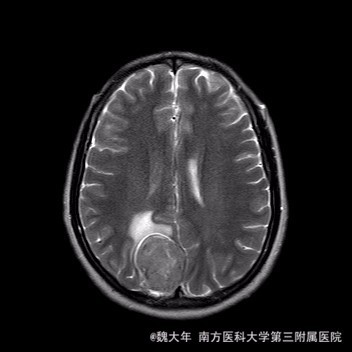

52岁,女性,因“反复头痛10余年,加重1年”入院。患者10余年前无明显诱因始出现头痛,表现为全头发作性胀痛,反复发作,无伴头晕、恶心,无呕吐、肢体抽搐,自行服药(具体不详)及休息后缓解,未予特殊处理。1年前患者觉头痛逐渐加重,以右顶部为甚,劳累或日晒后加重,无头晕、视物旋转,无恶心、呕吐,无发热、寒战,休息或平躺后症状稍有缓解,自行服药不能改善,至当地医院就诊,查颅脑MRI和CT提示“右侧顶部脑膜瘤”。

行“右顶开颅右顶部矢状窦旁脑膜瘤切除术”。取右顶马蹄形手术切口 ,颞侧翻开皮瓣,电刀切开骨膜,中线矢状缝上前、后极各钻一孔,颞侧后方钻一孔,铣刀铣一长方形(7*6cm)骨瓣,见硬膜表面较多点状渗血,予充分止血,悬吊硬膜。 显微镜下切除肿瘤:沿肿瘤边缘剪开硬膜后,见一大小约5*5*6cm肿瘤,沿硬膜内侧面呈匍匐状生长,边界与脑组织有蛛网膜分隔,质地较韧,基底与矢状窦关系密切,靠内侧与大脑镰粘连紧密,血供丰富。仔细分离肿瘤与脑组织的粘连,全切除肿瘤。肿瘤基底与矢窦粘连紧密,并破坏矢状窦侧壁,予低功率电刀反复烧灼,直至肿瘤无明显血供表现。严密止血后常规关颅。

术后1周复查头颅MR未见明显肿瘤残留,拆线后出院。